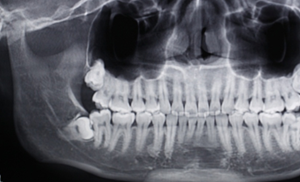

右下智齒去骨范圍如何?分冠線如何?怎樣才能最快時(shí)間能把這顆牙拔出來?

阻生牙的阻力分析及去除阻力的方法問題一:這顆智齒去骨范圍如何?分冠線如何?

答:本x線片示48近中低位埋伏阻生,且牙根緊鄰下牙槽神經(jīng)管,拔除時(shí)需注意充分去除近中方向的牙體冠方阻力及遠(yuǎn)中的牙槽骨阻力,挺出牙根時(shí)盡量做到一次完成,減少牙根與神經(jīng)管的摩擦,降低神經(jīng)受損風(fēng)險(xiǎn)。